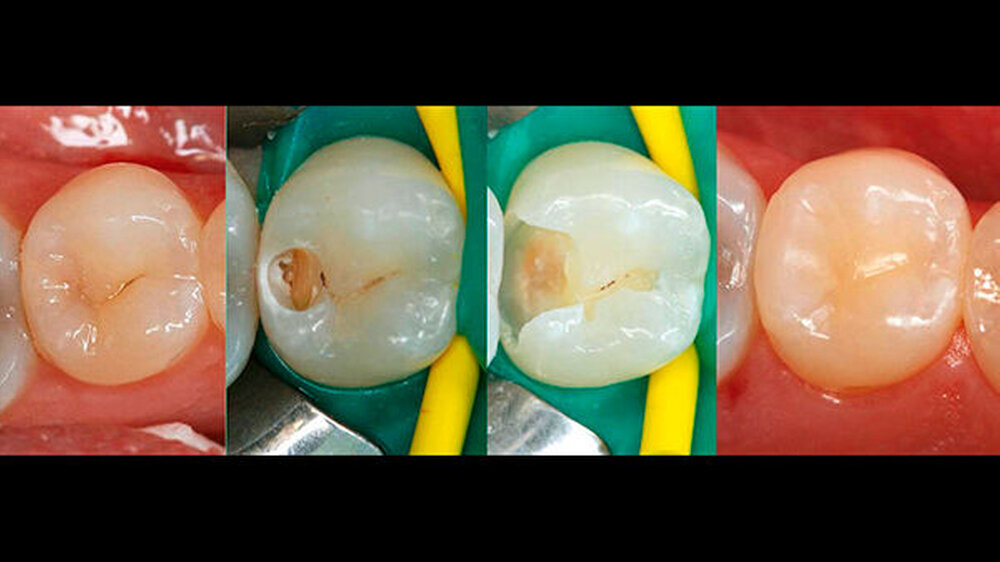

Neben der Prophylaxe der Karies ist es eine der Hauptaufgaben der restaurativen Zahnerhaltung, Karies zu entfernen und Defekte der Zahnhartsubstanzen wieder zu beseitigen. Nun wäre es bei einer prophylaktisch ausgerichteten Zahnheilkunde sehr sinnvoll, gerade bei der Ersttherapie der Karies möglichst viel gesunde Zahnhartsubstanz zu erhalten und nicht einer „einfacheren Kariestherapie“ zu opfern. Also sollte „extension for prevention“ als Black‘sche Präparationsrichtlinie bei der Primärversorgung nicht mehr angewandt werden [2]. Die iatrogene Entfernung gesunder Restzahnsubstanz sollte doch heute nur dann geschehen, wenn es für die Zugänglichkeit (Kariesentfernung) unbedingt erforderlich ist (Abb. 2/3). Auch für eine folgende plastische Füllungstherapie ist ein Belassen kariesfreier Schmelzanteile sinnvoll, weil gerade dann eine leichtere Gestaltung des approximalen Kontaktbereiches möglich ist (Abb. 2). Hilfsmittel wie schallgetriebene Präparationsansätze lassen heute ohne Weiteres auch eine unter‧minierende Präparation zu [3].

Wenn man die Bilderserie genau betrachtet, die für dieses Konsensuspapier mitveröffentlicht wurde, so kann davon ausgegangen werden, dass es sich bei dem vorgestellten Fall um eine approximal unter‧minierende tiefe Dentinkaries handelte, wobei okklusale und auch approximale, nicht kariöse Schmelzanteile der durchgeführten Kariestherapie zum Opfer gefallen sind. Warum auf den gezeigten Bildern nach Art von „extension for prevention“ eine Kavität frei von Unterschnitten erzeugt wurde, lässt sich aus unserer Sicht wenig mit einem präventionsorientierten Therapiegedanken in Einklang bringen. Wie bereits Elderton [4, 5] postulierte, ist nicht die Karies der „Hauptzerstörer“ von Zahnhartsubstanz, sondern der zahnärztliche Bohrer.

Geht man davon aus, dass bei einer unvollständigen Kariesentfernung auch der adhäsive Verbund zur kariösen Restzahnsubstanz deutlich reduziert ist [6, 7], dann ist es gerade für eine solche Konsensusempfehlung wenig hilfreich, ein heute überholtes oder auch in großen Teilen falsches klinisches Vorgehen (weite Extension) bildlich zu dokumentieren bzw. zu empfehlen und mit einer unvollständigen Kariesexkavation zu kombinieren.